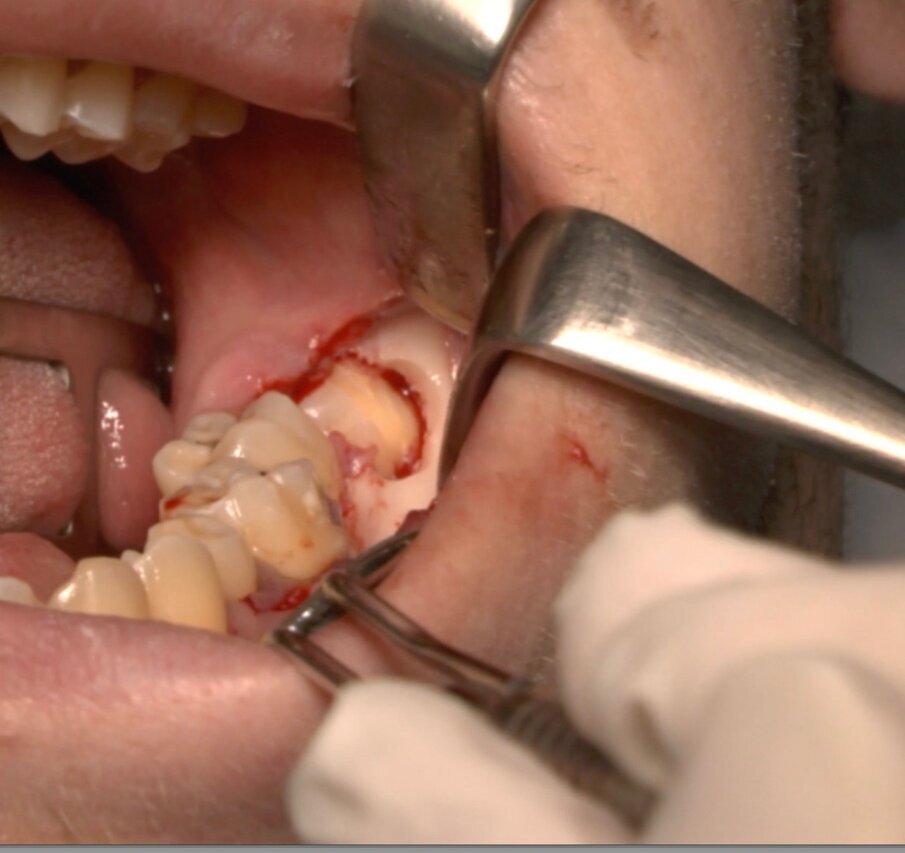

Protocollo standard

Ai pazienti viene prescritta una profilassi antibiotca con 2 gr di amoxicillina 1 h prima dell’intervento, si esegue quindi un anestesia di tipo tronculare con lidocaina senza vasocostrittore, poi infiltrazione di tipo plessica con adrenalina in corrispondenza del nervo buccinatore. Si scolpisce quindi un lembo a tutto spessore di tipo triangolare con incisione orizzontale alla base delle papille tra sesto e settimo ed incisione di scarico distale con andamento vestibolare (Figg. 1-4). Si procede con l’osteotomia che può essere eseguita con strumenti rotanti montati su manipolo retto oppure con terminale piezoelettrico con gli inserti dedicati. Qualora sia necessario si effettua l’odontotomia e la separazione radicolare con frese al carburo di tungsteno montate su turbina, quindi si esegue la lussazione e l’avulsione dell’elemento dentario. Si procede alla revisione della cavità alveolare con abbondante lavaggio con soluzione fisiologica, riempimento con collagene e sutura a punti staccati in seta 4/0. Il paziente viene dimesso con terapia analgesica ed antibiotica di supporto (Figg. 5-15).

Fig. 3_Disegno del lembo triangolare.

Fig. 4_Scheletrizzazione con visione della corone del 3.8.